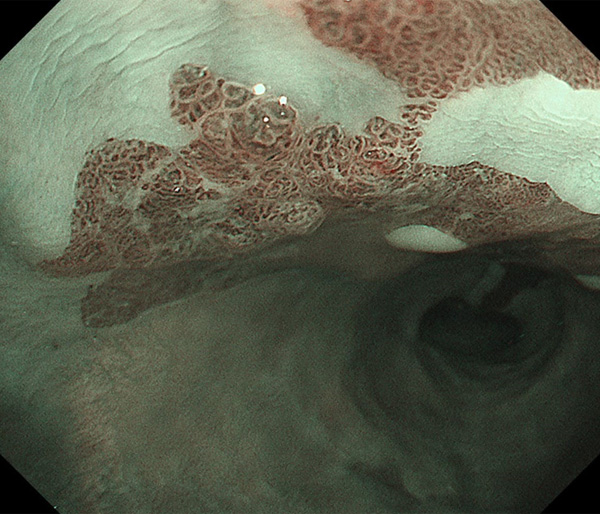

内視鏡所見と病理組織像の1対1対応が可能な症例を公募いたします。主にLSBEに発生した早期癌(HGDを含む)を対象としますが、興味深い症例であればSSBE癌でも結構です。採否は世話人へご一任ください。

症例呈示希望者は応募用紙に記入の上、代表的な内視鏡(2枚)、切除標本(新鮮、固定)、切り出し図、マッピング、代表的組織像とともに、Barrett 食道研究会事務局 barrett.shinshu@gmail.comへお申し込み下さい(10MB以下でお願い致します)。

特に、本邦では極めて稀なlong segment Barrett’s esophagus(LSBE)から発生した早期癌は、診断に難渋する場合も多く、欧米ではランダム生検による検出が標準的とされています。背景のBarrett食道もろとも全体を内視鏡切除+ラジオ波焼灼する欧米と異なり、ESDで内視鏡的な局所切除が基本の本邦では、存在診断+範囲診断(特に水平)を的確に行うことが不可欠です。

そのためには、一流の病理医による組織学的診断とエキスパート内視鏡医による拡大内視鏡像との一対一対応を徹底的に行うことで、『本来、見えないであろう拡大所見の先にある組織構築像が診えてくる』所まで内視鏡診断レベルを上げていく必要があります。その実現には、一対一対応を追究した症例(特にLSBE発生例)1例でも多く経験するしかありません。本研究会でBarrett食道腺癌(LSBE発生早期病変)を共に学び、拡大内視鏡像の一歩先を診るスキルを習得しましょう!一人でも多くの皆様のご参加をお待ちしています。

海外で講演やライブを行う度に、日本と欧米ではBarrett食道癌診断法に大きな乖離がある事を実感します。なぜ、彼らは内視鏡で診断せず、ランダム生検に頼るのか?

私は、Barrett食道癌はHGDも含め、内視鏡による存在診断、範囲診断が可能と信じて来ました。しかし最近、NBI拡大観察を併用しても側方範囲診断が不可能なLSBE症例を経験しました。診断技術を向上させるためには、多くの症例を診るしかありません。そこで、Barrett食道に造詣の深い先生方に世話人をお願いし、Barrett食道研究会を立ち上げることに致しました。全国からLSBE症例を集め、内視鏡的、組織学的診断に迫りたいと思います。皆様のご参加をお待ち致します。